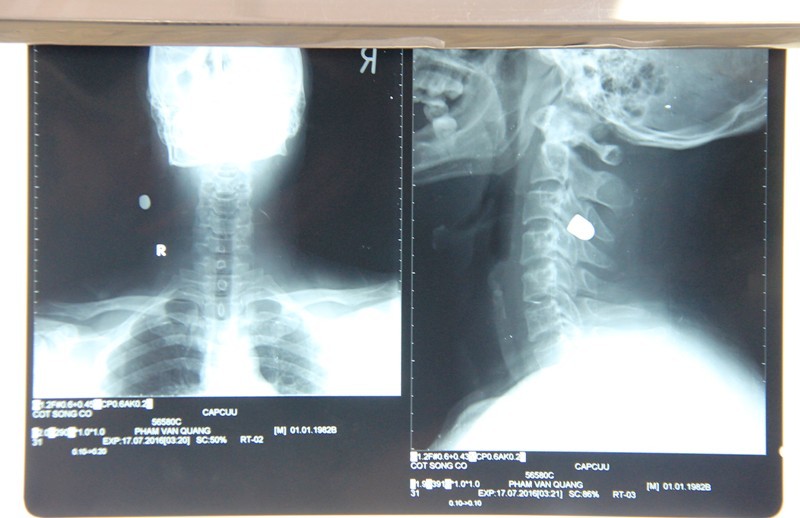

Viên đạn mắc vào cổ phải bệnh nhân Phạm Văn Quang. |

Theo bác sĩ Dũng, vào 1h30 ngày 17/7, bệnh nhân Quang nhập viện cấp cứu trong tình trạng bị viên đạn bắn từ vùng má trái, xuyên qua họng và nằm cổ bên phải.

Qua thăm khám, hội chẩn, tới 10h cùng ngày, các y bác sĩ đã quyết định mổ để gắp viên đạn ra ngoài.